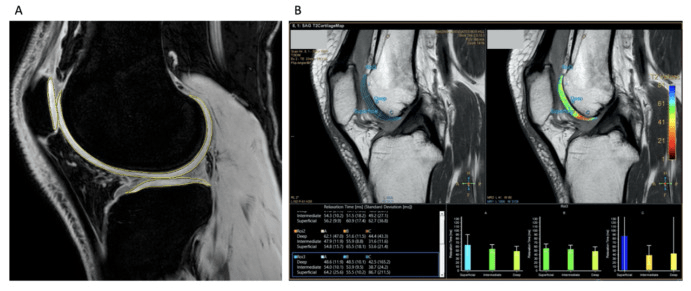

圖2:定量圖像MRI分析

• MAG200隊列報告的反應者比例高于安慰劑組,并且疼痛癥狀有臨床和統計學顯著改善,所有KOOS分量表均有臨床相關改善。(圖2)

• MAG200顯示出優于安慰劑的可重復治療效果,這對于10×106劑量組的疼痛具有臨床相關性,對于20×106和100×106劑量組的功能具有臨床相關性。

• 在MAG200 10、20和100 × 106劑量組中,觀察到疾病改善趨勢,膝關節軟骨總體積有所改善,而安慰劑組中骨關節炎有輕微改善。

綜上所述,在MAG200 10、20和100 ?× ?106劑量組中,觀察到疾病改善趨勢,膝關節軟骨總體積有所改善,而安慰劑組中骨關節炎進展不顯著。